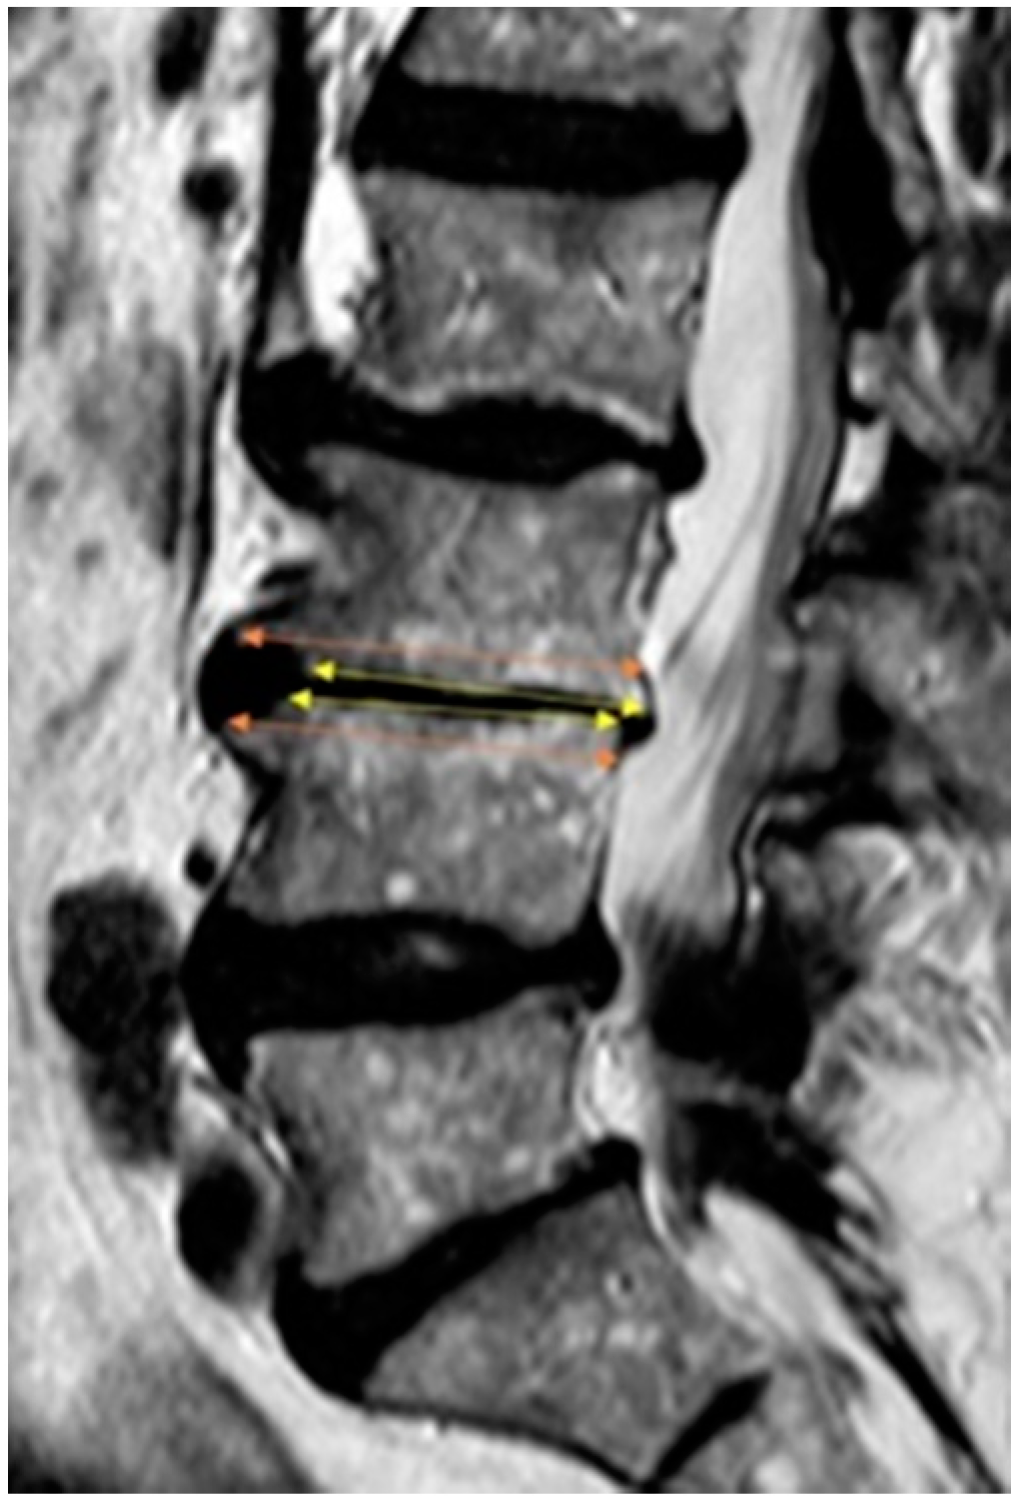

2.6. Measurement

2.7. Theory/Calculations